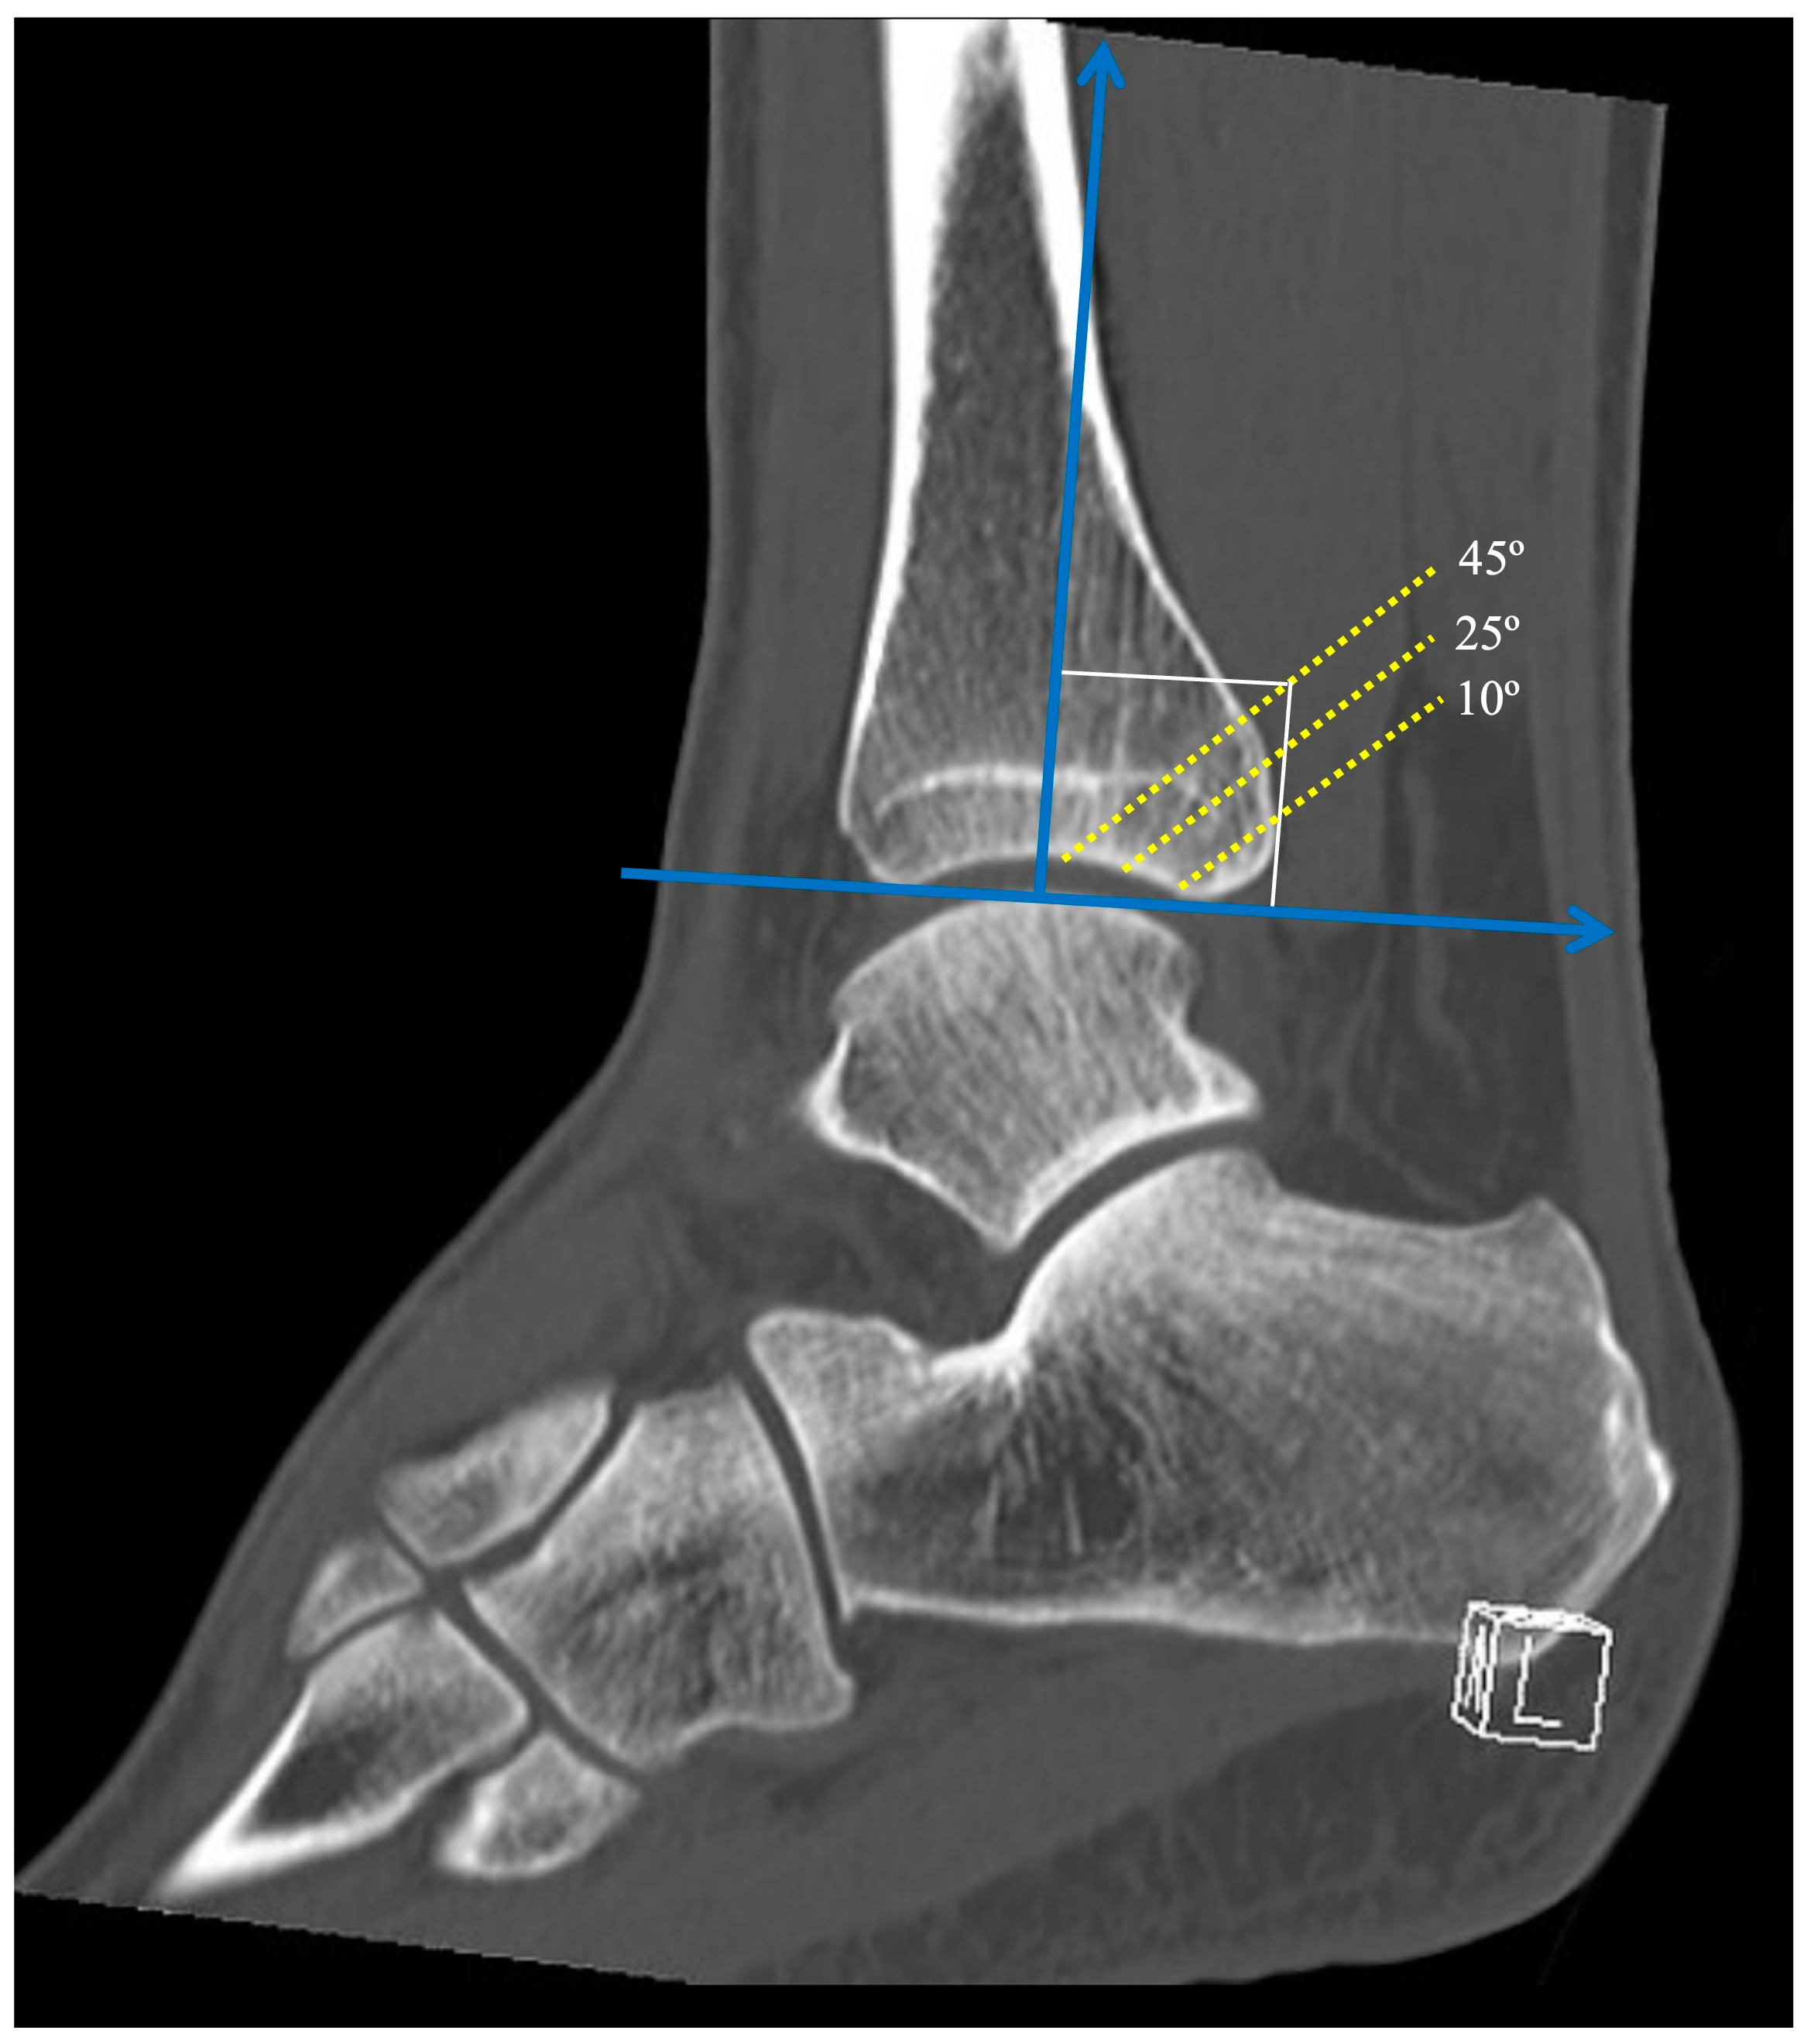

The angle between the fracture line and the Z axis on the sagittal reconstruction images was defined as the sagittal angle of the posterior malleolus fracture (Figure 3). Taking the Z axis in the sagittal reconstruction images, three different fracture lines of the posterior malleolus were defined, with sagittal angles of 10º, 25º, and 45º. The sagittal angles were defined to simulate a fracture line considered stable (10º), a fracture line that affects the fibular notch (25º), and a fracture line that affects a large part of the tibiotalar loading area (45º), representing a tibial pilon.

Figure 3. The angle between the fracture line and the Z axis on the sagittal reconstruction images was defined as the sagittal angle of the posterior malleolus fracture. Note the three different sagittal angles with fragments involving 10º, 25º, and 45º of the articular surface.